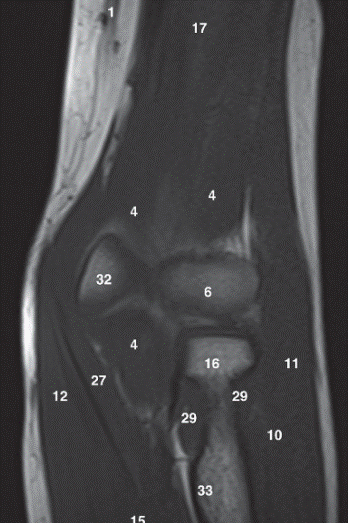

Q

Label 1,4,6,16,32,33

A

1-Lt. Basilic vein

4=-Lt. Brachialis muscle

6-Capitulum of Lt. humerus

16=Head of Lt. radius

32-Trochlea of lt. humerus

33= Tuberosity of lt. radius

Label 6,16,17,18,22,25,32

6=Capitulum of lt. humerus

17=Lt. Humerus

18=Lateral condyle (lt. humerus)

22=Medial condyle (rt. humerus)

25=Olecranon fossa of lt. humerus

32=Trochlea of lt. humerus

Label 19 and 26

19-Lt. Triceps brachii muscle

26-Olecranon process of lt. ulna

Label 3,6,8,8,16,17,19,25

3=Biceps brachii muscle

6=Brachialis muscle

8=Capitulum of humerus

9=Cephalic vein

16=Radial head

17=Humerus

19=Triceps brachii

25=Radius

Label 3,6,9,17,21,23,28

6-Brachialis muscle

9=Coronoid process

21=Triceps brachii

23=Olecranon process of ulna

28-Trochlea of humerus